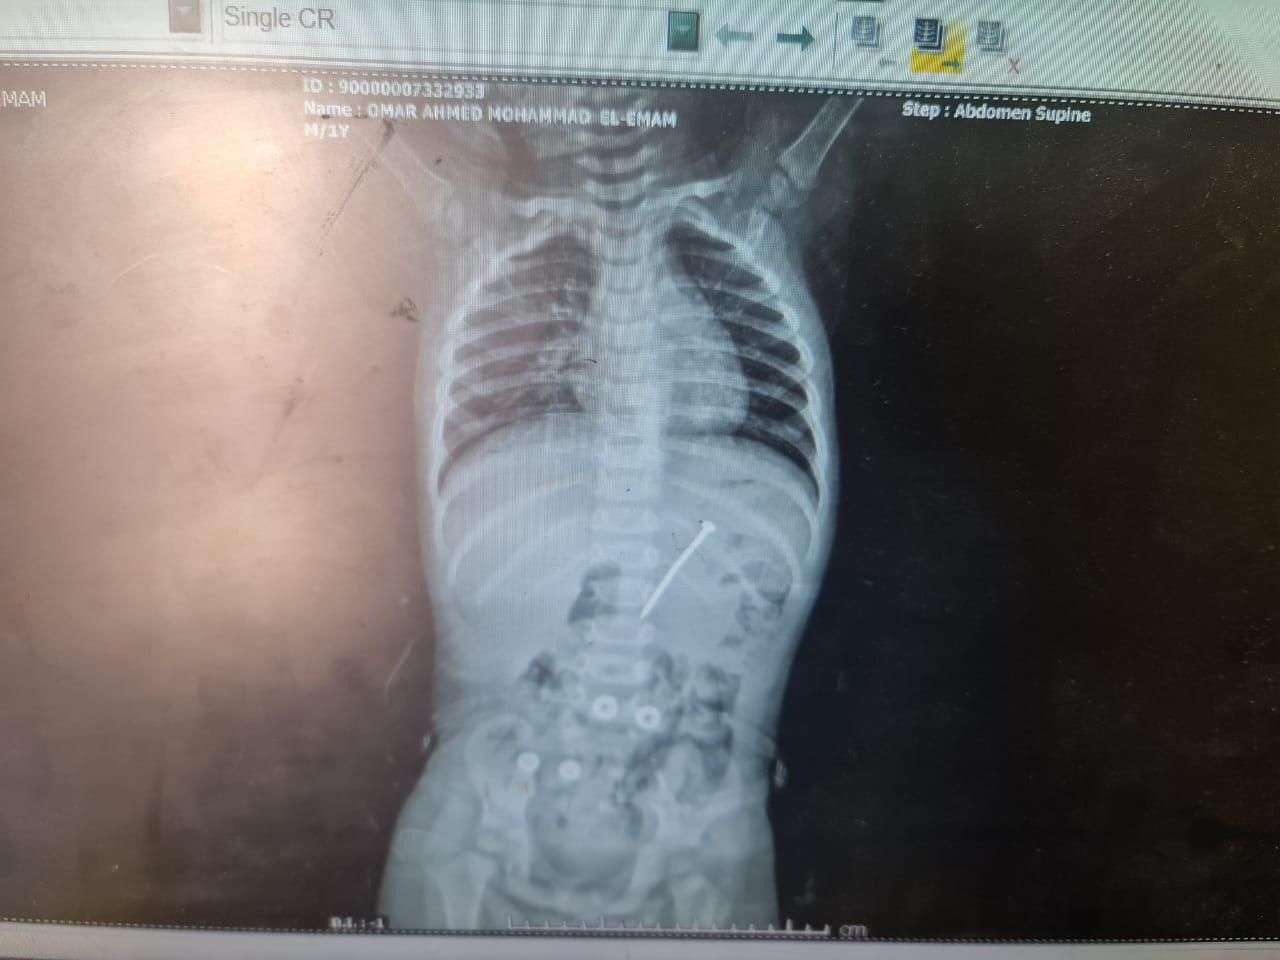

وقال الدكتور أحمد مجاهد، أستاذ طب الأطفال أمراض الكبد ومناظير الجهاز الهضمي، إن الطفل عمره عاما و5 شهور، وصل إلى المستشفى مساء الخميس الماضي، وأكد والده أن الطفل ابتلع مسمارا حديديا، وبإجراء الأشعة اللازمة تبين وجود المسمار في منطقة الاثنى عشر.

وأضاف مجاهد، أن المسمار عبر المعدة، ووصل إلى الاثنى عشر، وكان لابد من إجراء طارئ فتم صيام الطفل وتحضيره لإجراء المنظار، وتمكن الفريق الطبي من استخراج المسامر وطوله 6 سم من اثنى عشر الطفل بعد عمليه لم تستغرق سوى 5 دقائق، والطفل في حالة صحية جيدة وتصرح له بالخروج من المستشفى.